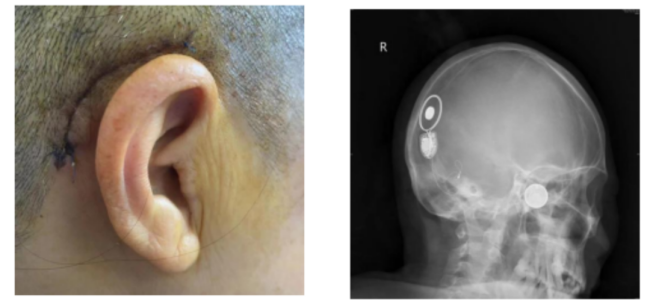

李女士接受人工耳蜗植入术后的影像图片

耳鼻咽喉头颈外科专家团队为李女士进行了右侧人工耳蜗植入手术。术中,手术团队对植入的电极进行了电极阻抗测试和神经反应遥测(NRT),均提示人工耳蜗电极工作良好,电阻正常,神经反应良好,手术顺利完成。如今术后1个月过去了,植入的人工耳蜗开机调试,李女士对声音反应好,连连感谢专家团队实施手术和精心护理,让她能清晰听见这个世界的声音。